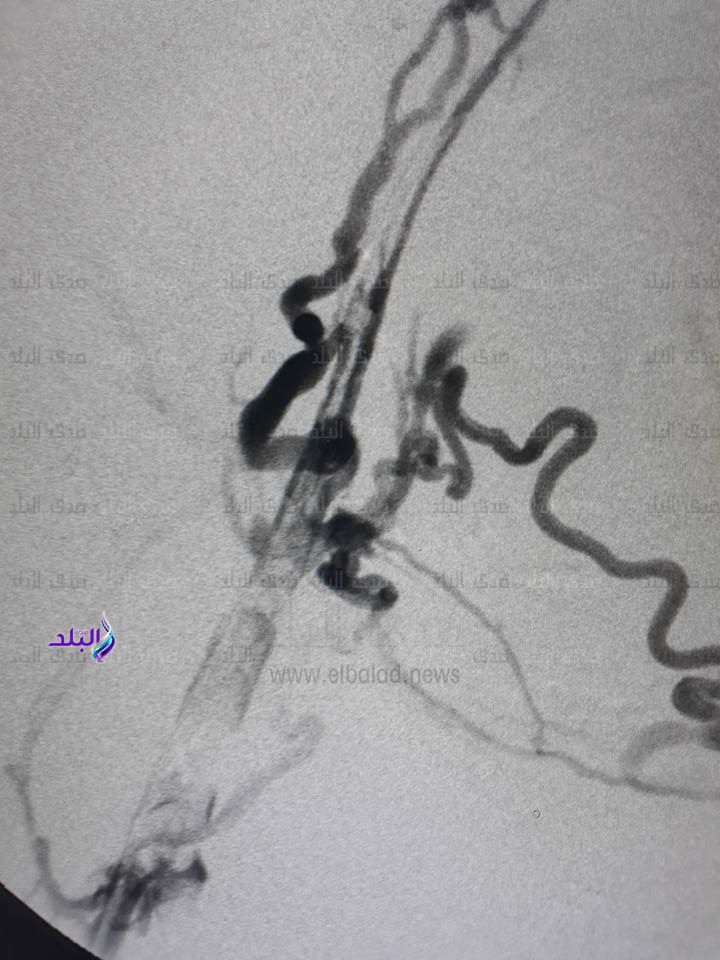

وحول تفاصيل القسطرة أوضح الدكتورعثمان محمود أحمد مدرس جراحة الأوعية الدموية بكلية الطب والمسئول عن إجراء القسطرة أنه تمّ إجراء أشعة دوبلكس عاجلة للمريضة تبين من خلالها وجود إنسدادات مزمنة بالإضافة إلى وجود جلطة حادة وانسداد تام بكل الأوردة بطول الساق والفخذ والوريد الحرقفى ممتدة حتى الوريد الأجوف السفلى , مضيفًا أنه تمّ مناقشة إمكانية محاولة إذابة الجلطة بمذيبات الجلطة رغم صعوبتها في وجود إنسدادات قديمة مزمنة , وكذلك عمل شق داخل الإنسدادات وتركيب قسطرة الإذابة بنجاح عن طريق القسطرة التداخلية بدون جراحة وتم إذابة الجلطة على مدار 48 ساعة , ثم إعادة التصوير بالقسطرة التداخلية والتعامل مع الإنسدادات المزمنة بعد الإذابة الكاملة للجلطة الحديثة وعمل توسيع بالبلون وتركيب دعامة ذاتية الانفتاح خاصة للأوردة بالوريد الحرقفى الأيسر وإعادة الاتصال الدموى وسريان الدم بكل الأوردة التى كانت بها انسدادات وإعادة الوريد الى الوظيفة الطبيعية بصورة ناجحة , وذلك بالتعاون مع الدكتور محمد جمال جلال المدرس المساعد بالقسم .

وفي السياق ذاته أكد الدكتور عثمان أن المريضة خرجت من المستشفى الجامعى بعد إجراء القسطرة بـ24 ساعة فى صحة جيدة , وموضحًا أن صعوبة الحالة كانت تكمن فى الانسدادت المزمنة بسبب عدم إذابة الجلطة السابقة والتى كان لها تأثيرها البالغ على المريضة من خطورة تكرار الجلطات وخطورة حدوث جلطات بالرئة , مشيدًا في ذلك بجهود إدرارة المستشفى الجامعي وأعضاء هيئة التدريس بقسم جراحة الأوعية الدموية في تقديم الدعم التقنى والمشورة الفنية اللازمة وكذلك تذليل كافة العقبات والصعوبات التي من شأنها عرقلة إجراء مثل هذه الحالات والجراحات النادرة .